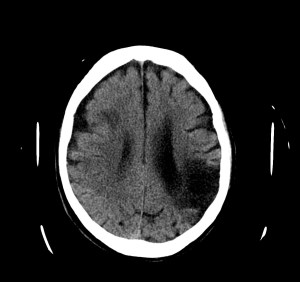

Se realiza un TC de cráneo sin contraste, estos son los hallazgos:

Esta imágen plantea dudas, puede ser una masa o un foco de sangrado, es más, si de esta segunda imagen asumimos que la zona de densidad aumentada corresponde a un sangrado, la pregunta a realizarse ahora es ¿de qué tipo? ¿Es un sangrado intraparenquimatoso, una transformación hemorrágica de un infarto o es otra cosa?